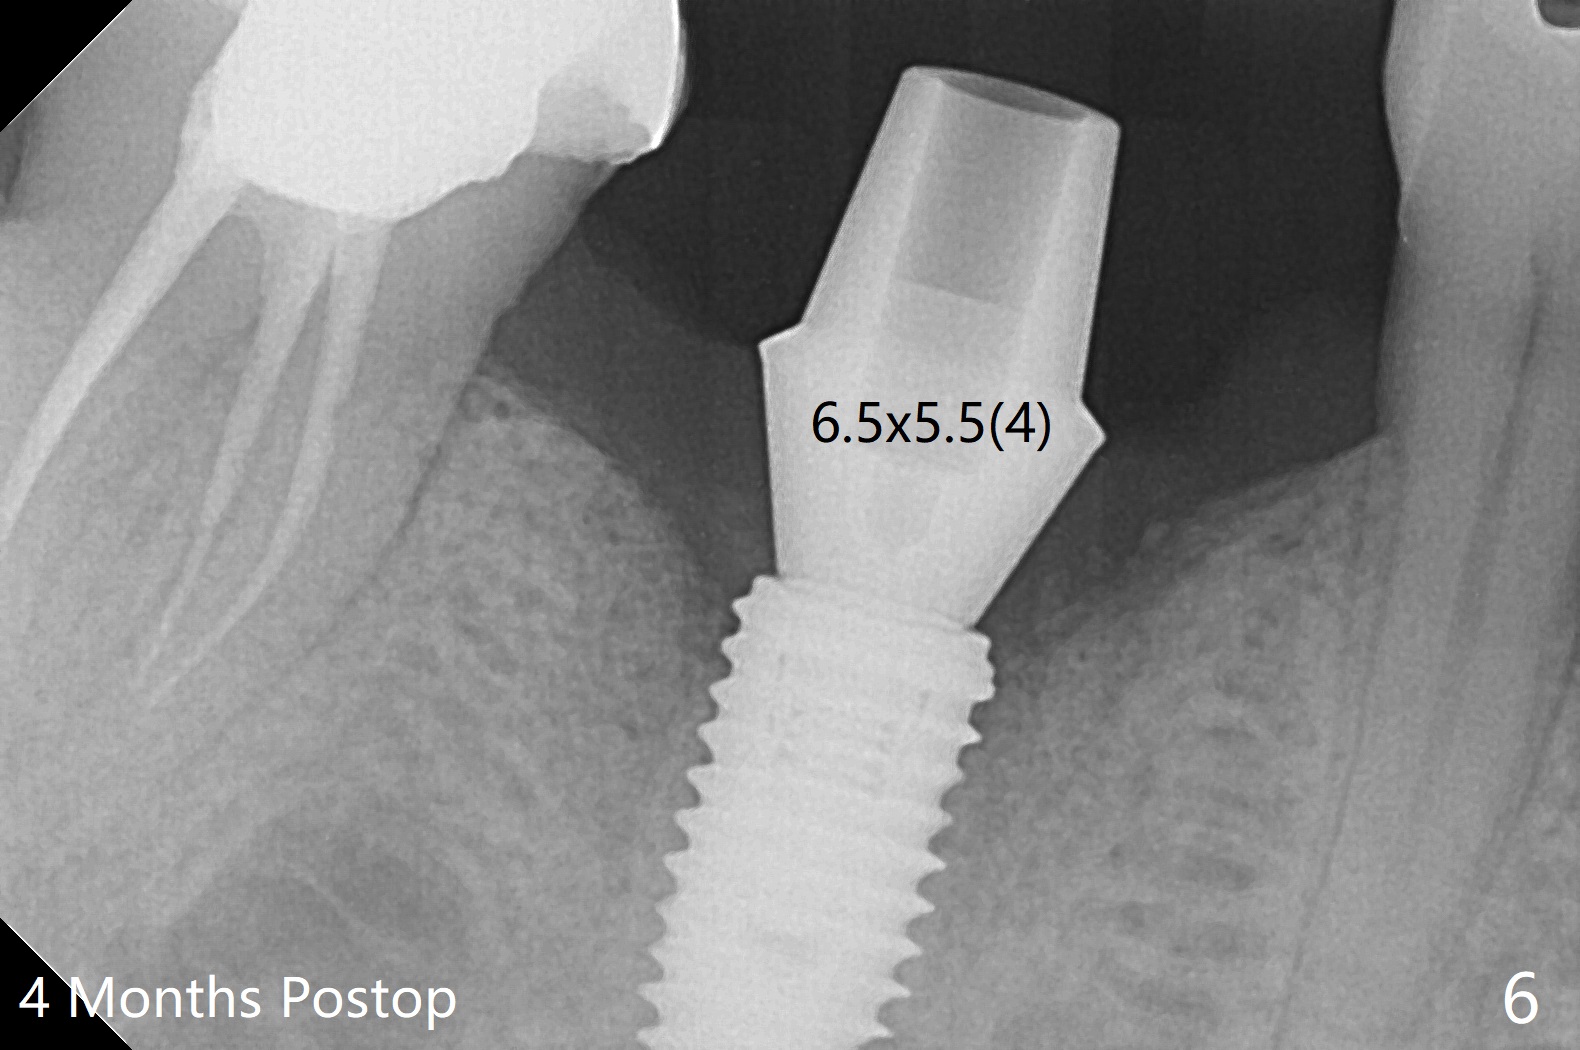

The sockets of #30 (M) of a smoker (M) are apparently not healing ~ 2 months post extraction (Fig.0, 0'). The ridge looks wide 3 months post extraction without bone graft in other office before (Fig.1) and after (Fig.2) flap surgery. The socket appears to have healed perfectly consi-dering buccal defect (M) revealed by CT ~ 1 month earlier. When a 5x10 mm implant is placed with guide and high torque (in spite of overprep), granu-lation tissue is found mesio-buccal (MB, Fig.2 *). After curettage, bone graft is placed around the implant, especially MB (Fig.3 *), followed by PRF. Periodontal dressing dislodged a few days postop because of mastication on the right side (Fig.4), whereas the anterior one (24/26) remains in place. There is a small gap around the implant when it is uncovered (Fig.5 arrowheads). It appears that some of bone graft gets lost from the incision (smoker). A 6.5x5.5(4) mm cemented abutment is seated and torqued at 30 Ncm before impression (Fig.6). There is no bone loss 11 months post cementation (Fig.7).